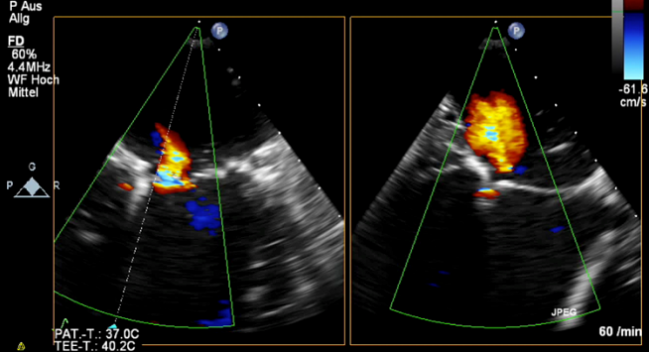

Photo Credit: Baldus S. Two case Presentations: one highly successful and one highly unsuccessful MitraClip in secondary MR. Presented at: TCT 2018. September 23, 2018. San Diego, CA.